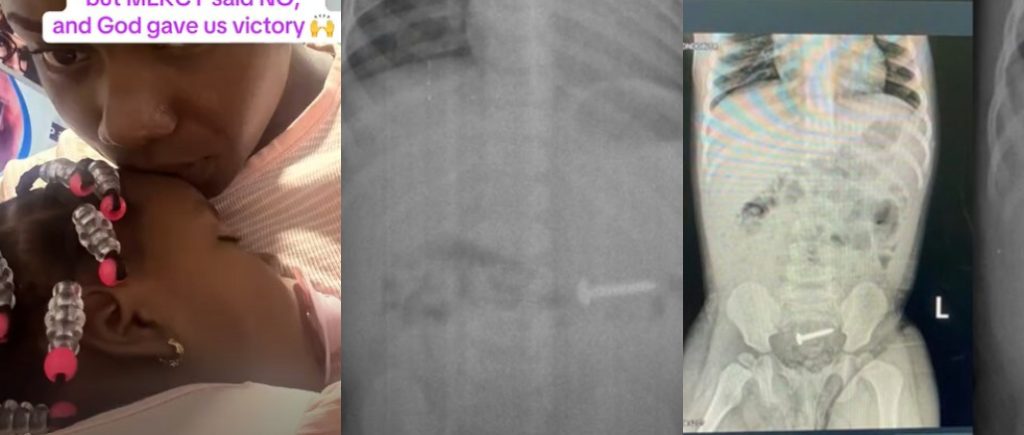

• A mother has shared how her one-year-old daughter, who accidentally swallowed a nail, was scheduled for surgery but miraculously passed it out naturally.

According to her, doctors confirmed the object was stuck in the child’s system and quickly prepared her for surgery. The news left the worried mother in fear, as the thought of her little girl undergoing such a risky procedure was overwhelming.

However, in a surprising turn of events, the child eventually passed the nail naturally through her stool only hours later, eliminating the need for surgery.

Sharing her testimony, the grateful mother said, “Mercy said no, and God gave us victory.”